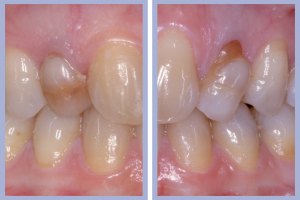

Nel presente caso clinico si tratta della sostituzione implanto-protesica di due incisivi laterali superiori agenesici in una Paziente di sesso femminile. L’agenesia degli incisivi laterali era associata a mesio-dislocazione dei canini al posto degli incisivi laterali e dunque l’obiettivo terapeutico era rappresentato dalla sostituzione dei denti mancanti in zona canina e dalla trasformazione protesica dei canini permanenti presenti in incisivi laterali.

L’esame clinico iniziale (Figg. 1, 2) metteva in evidenza una buona situazione dento-parodontale generale; l’igiene orale e la collaborazione da parte della paziente, fortemente motivata alla soluzione del problema, erano ottime. L’esame radiologico ortopanoramico iniziale (Fig. 3) mostrava una buona quantità di osso apicalmente alle radici degli elementi decidui che apparivano sottili e parzialmente riassorbite. Il progetto terapeutico prevedeva un posizionamento implantare post-estrattivo immediato associato a carico immediato non funzionale tramite l’utilizzo di monconi temporanei e corone in resina precedentemente allestite, da ribasare in bocca dopo la preparazione dei monconi.

- Fig. 1 – Agenesia dei laterali superiori con mesio-dislocazione dei canini permanenti al posto degli incisivi laterali. Visione frontale

- Figg. 2a, b – Visioni laterali dei canini decidui

- Figg. 28a, b – Confronto tra inizio e fine trattamento